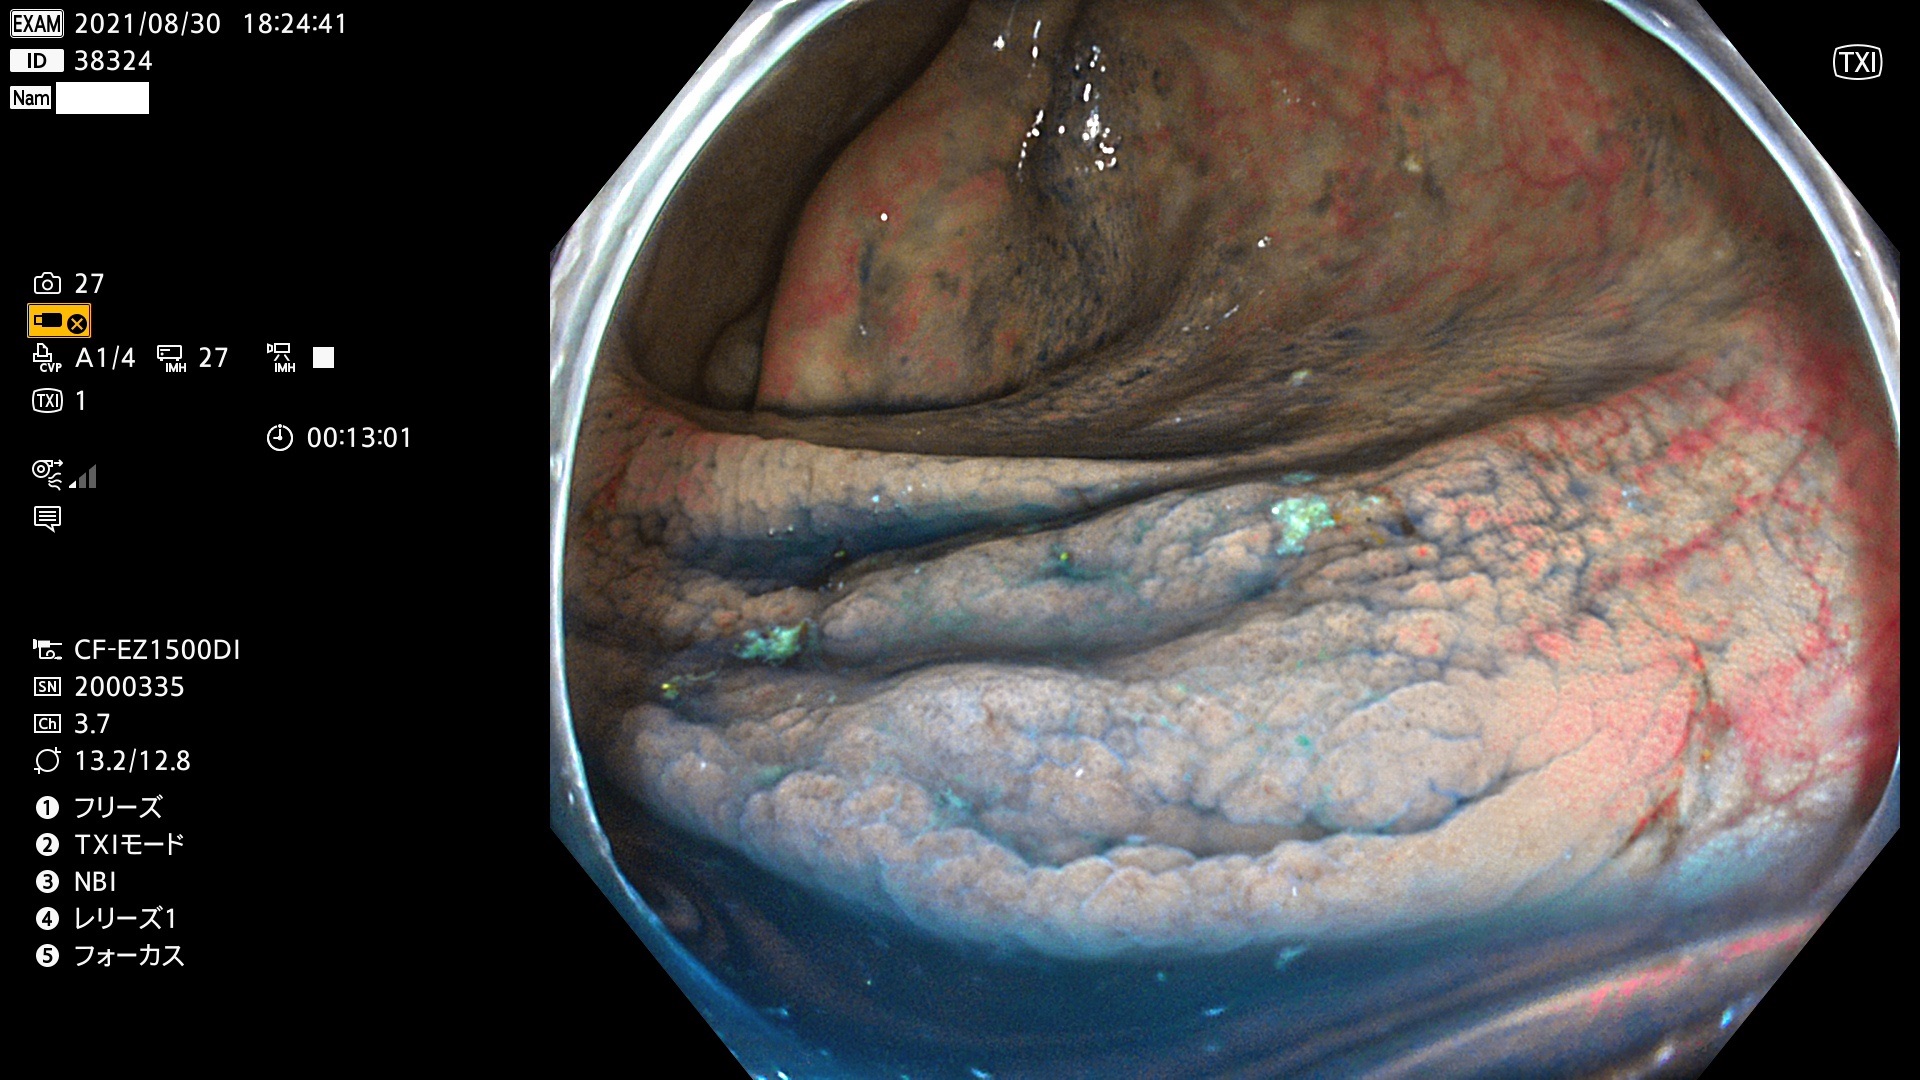

38300 38301 38302 38303 38304 38306 38307 38308 38309 38310 38311 38312 38313 38314 38315 38316 38317 38319 38321 38322 38323 38324 38325 38327 38331 38332 38333 38334 38337 38338 38339 38340 38341 38343 38346 38348 38349 38350 38351 38352 38353 38354 38355 38358 38359 38360 38361 38362 38363 38365 38366(SSAP) 38368 38369 38370 38371(SSAP) 38372 38374 38375 38376 38377 38378 38380 38381 38382 38383 38384 38385 38386 38388 38389 38391(SSAP) 38395 38397 38399

発見困難で危険性の高い平坦型病変(上記100名より抽出)